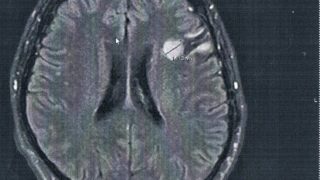

GLIOMA:手術後120ヶ月目の検査

手術から10年が経過した。半年ごとの定期検査です。検査概要びまん性星細胞腫グレード2(悪性転化しやすい腫瘍)MRI検査: 造影剤なし / 造影剤あり造影剤ありの場合:4時間前から絶食し、MRIの1時間前に血液検査を済ませる。診断結果初めて前...